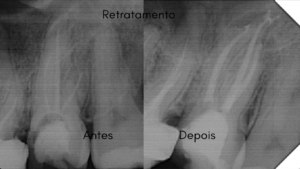

Alguns trabalhos